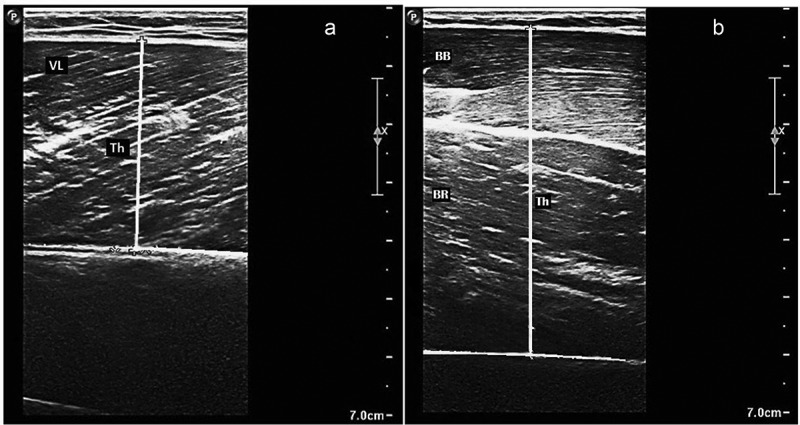

Methods: Forty-three middle-aged physically active individuals (26 peri- and post-menopausal females and 17 males) completed the study after being randomly assigned to one of the following intervention groups: pre-workout (PREW n = 24, 54 ± 4 years, body mass 77.6 ± 16.0 kg) or a carbohydrate-only comparator (COMP n = 19, 52 ± 4 years, body mass 80.6 ± 16.0 kg). Measurement of fat and fat-free mass (via plethysmography), waist and hip circumferences, muscle thickness (via ultrasound), strength, power output and muscle endurance performance were collected before and after a 6-week resistance training programme performed 3 times per week. Treatment consisted of ingesting 30g of the assigned supplement, mixed with 400mL of plain water, 15min before each workout session.

Results: Both groups significantly (p < 0.05) reduced fat mass (mean ± SD) (PREW -1.4 ± 1.6 kg; COMP -1.0 ± 1.5 kg), increased fat-free mass (PREW +0.9 ± 1.1 kg; COMP + 0.8 ± 0.9 kg); vastus lateralis (PREW +0.2 ± 0.2 cm; COMP + 0.1 ± 0.6 cm), and elbow flexors (PREW +0.5 ± 0.3 cm; COMP + 0.4 ± 0.2 cm) muscle thickness. Only the PREW group showed a significant reduction in the waist circumference (-1.8 ± 1.8 cm, p < 0.01). However, no significant differences between groups (PREW vs. COMP) were identified at post-intervention. Isometric force, countermovement jump, medicine ball throw, and upper and lower body muscle endurance performance improved (p < 0.05) for both treatments, with no difference between groups.